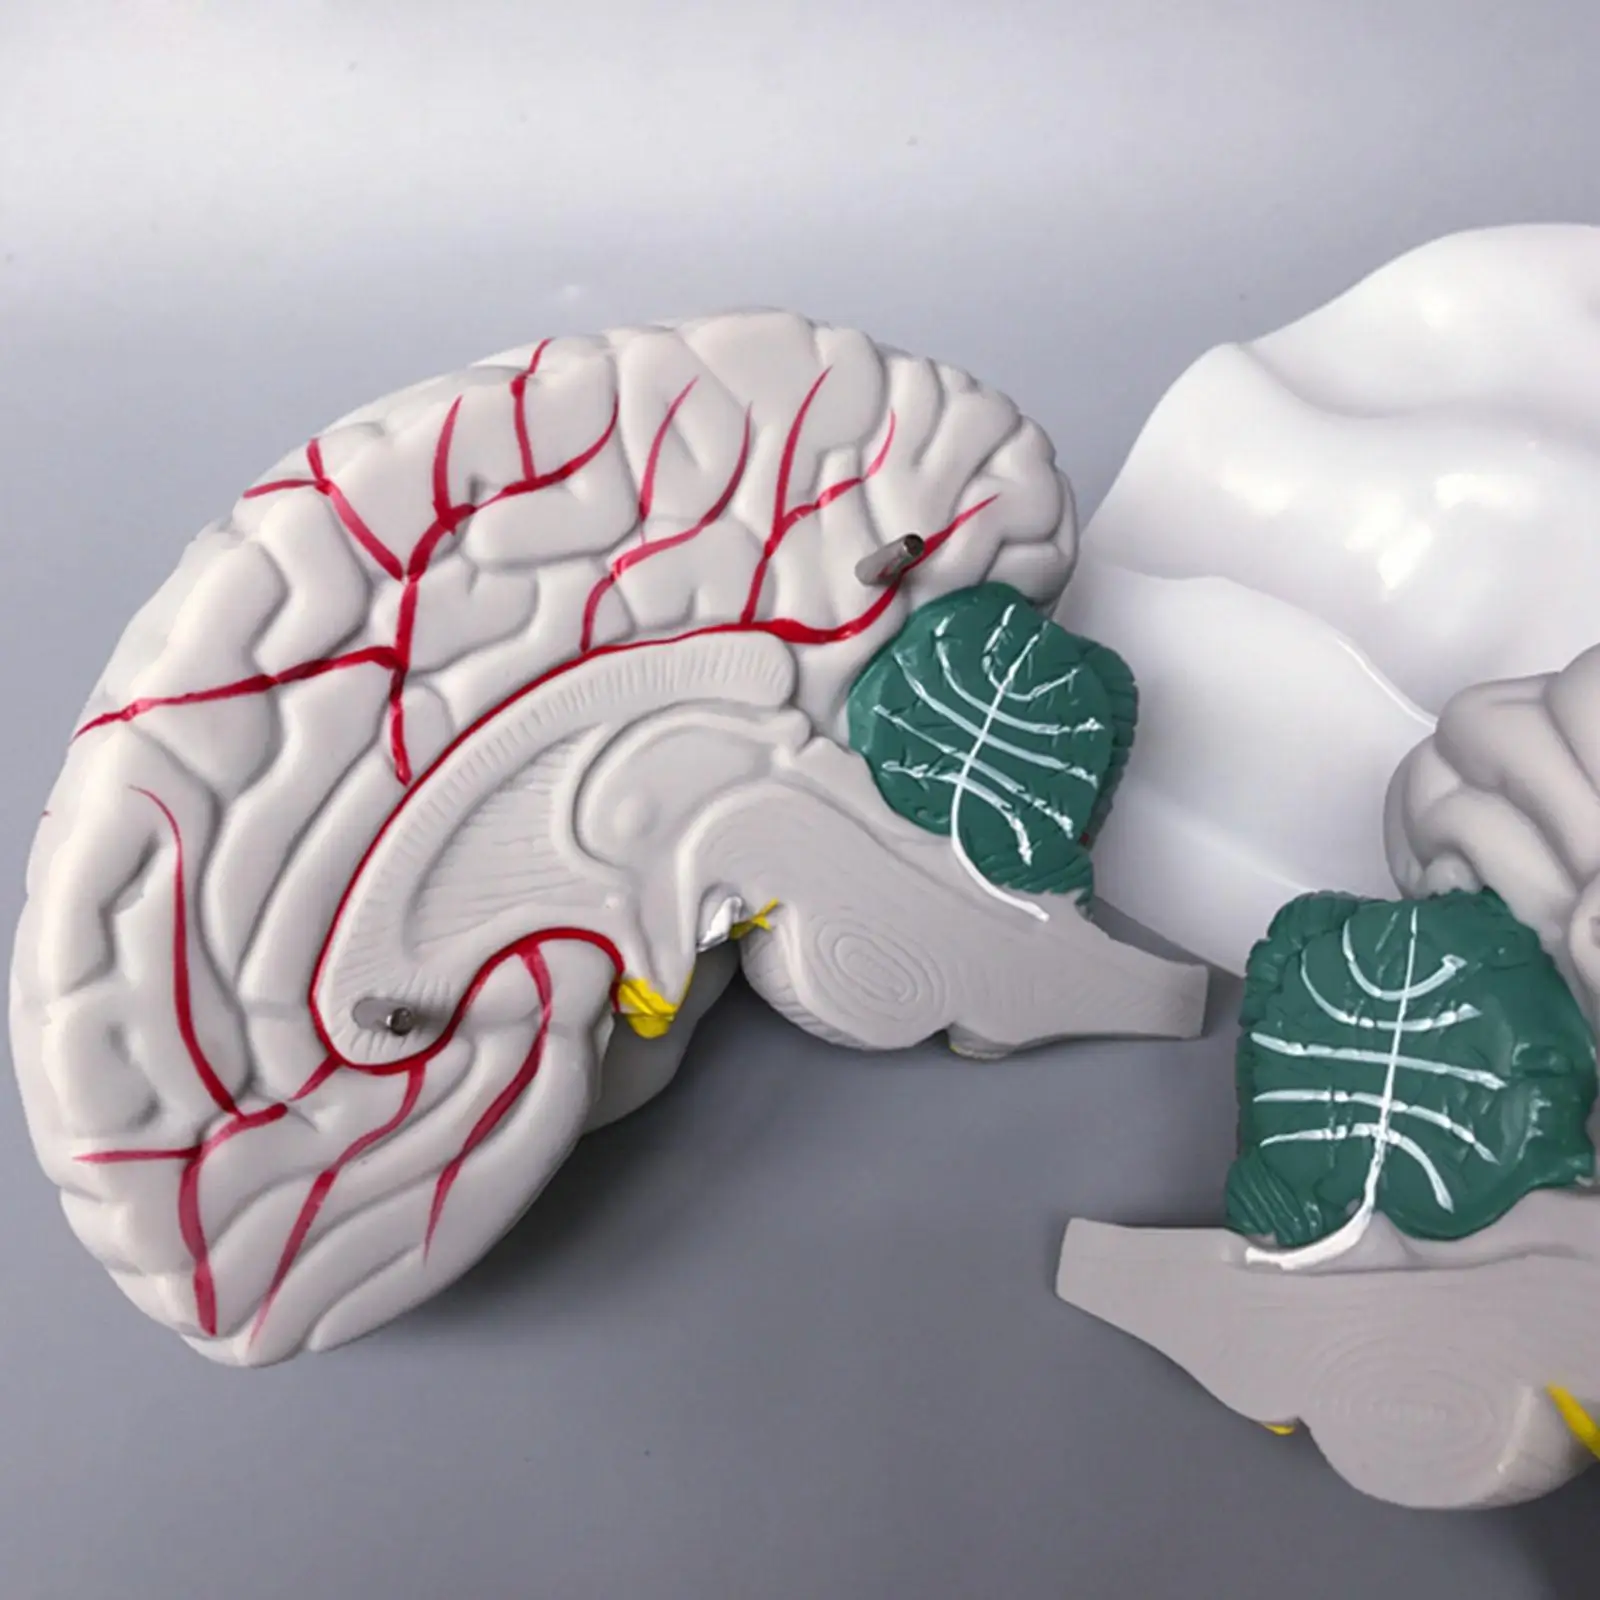

Сагиттальный разрез головного мозга (модель)